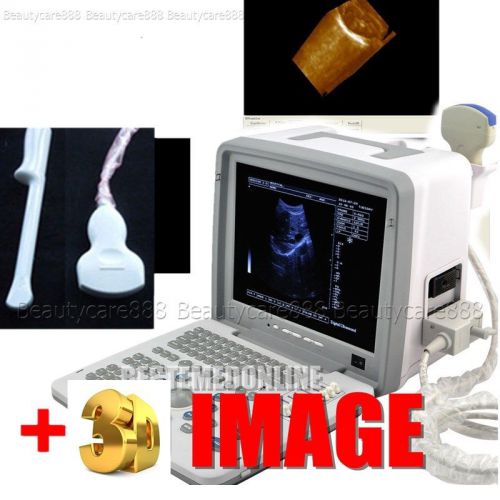

Brand | Ultrasound 9000E2 |

| MPN | Full Digital Ultrasound | ||

| Model | HIGH RESOLUTION | ||

Portable Digital Ultrasound Scanner Machine + Convex + Linear Probe +3D BID BID

Full Digital Portable Ultrasound Scanner Machine +Convex and TV probes free 3D